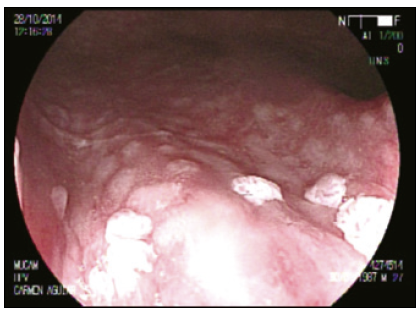

Cromoendoscopía digestiva magnificada en sustitución de la AAR convencional

La AAR en la literatura actual es sinónimo de colposcopía anal con tinción química.5, 7, 17, 18 Utilizando las nuevas tecnologías de la videoendoscopía digestiva es posible alcanzar una magnificación óptica de 200x, significativamente superior a la de un colposcopio de última generación. Nosotros trabajamos con una imagen magnificada de 100x que nos permite un mejor manejo del foco (Figuras 1 y 2).

El uso de capuchón es necesario al comienzo del entrenamiento. Con el advenimiento del sistema Laséreo, hemos sustituído la acetotinción por la cromotinción electrónica. Esto ha simplificado la técnica, acortando los plazos y las rotaciones del anoscopio, que pueden resultar molestas especialmente cuando hay hemorroides. El destaque de los cambios en el patrón vascular y glandular es igual de efectivo (Figura 3). El uso del colonoscopio permite valorar el recto, más allá del canal anal, con el fin de diagnosticar las metaplasias escamosas que pueden ser asiento de displasias VPH (Figura 4).

En cuanto a las tomas de muestras, el uso del fórceps de biopsia es sin duda menos cruento dado que presenta una apertura de 4 mm. En colposcopía se utiliza la pinza baby tischler; desconocemos las complicaciones de este procedimiento dado que no hemos encontrado trabajos publicados al respecto. Es una zona de difícil manejo para la biopsia dada la vascularización y la presencia de fibras nerviosas inmediatamente por debajo de la línea criptopapilar. La frecuencia de la patología digestiva asociada en el canal anal y el recto bajo (hemorroides, fisuras, abscesos, fístulas, pólipos) implica la necesidad de su conocimiento para el tratamiento de estas o sus complicaciones.